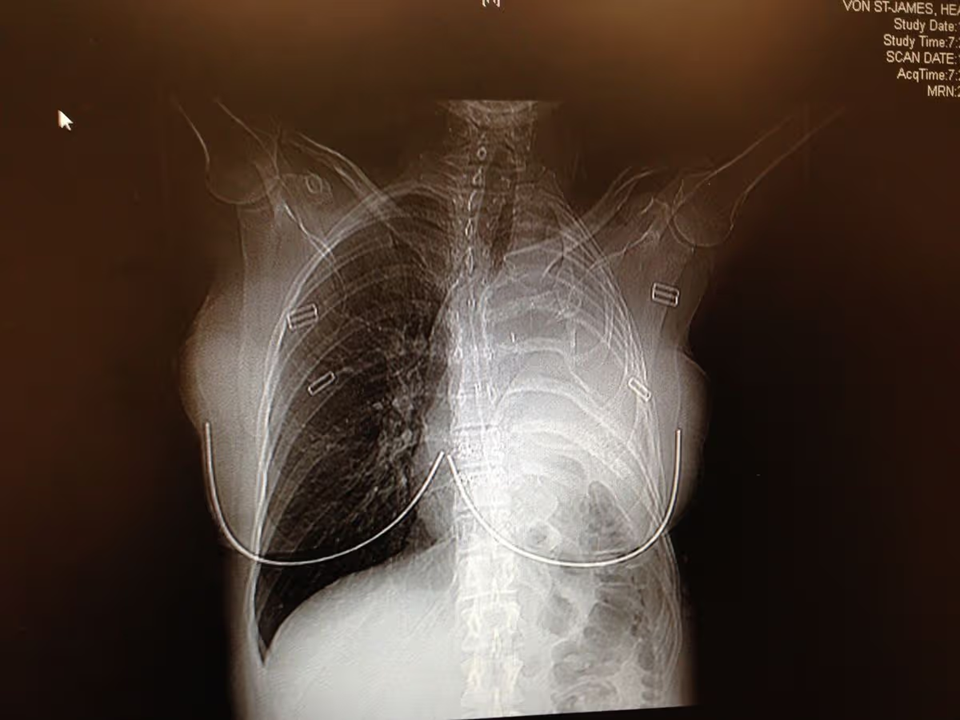

Sau nhiều thập kỷ, khi 36 tuổi và đang mang thai, Heather bắt đầu bị mệt mỏi mãn tính và sốt, phản ánh một bệnh lý tiềm ẩn. Chụp CT não và phổi cho thấy một khối u lớn và chẩn đoán cô mắc bệnh u trung biểu mô, một dạng ung thư ác tính do tiếp xúc trực tiếp với amiăng.

Vào thời điểm đó, các bác sĩ đã thông báo tin dữ rằng nếu không phẫu thuật, bà chỉ còn sống được khoảng 15 tháng. Điều này đã thúc đẩy bà quyết định theo đuổi phương pháp điều trị mà bà có khả năng thực hiện, bao gồm việc cắt bỏ phổi trái, màng phổi, một xương sườn và một phần cơ hoành và màng ngoài tim, tiếp theo là bốn đợt hóa trị và 30 lần xạ trị.